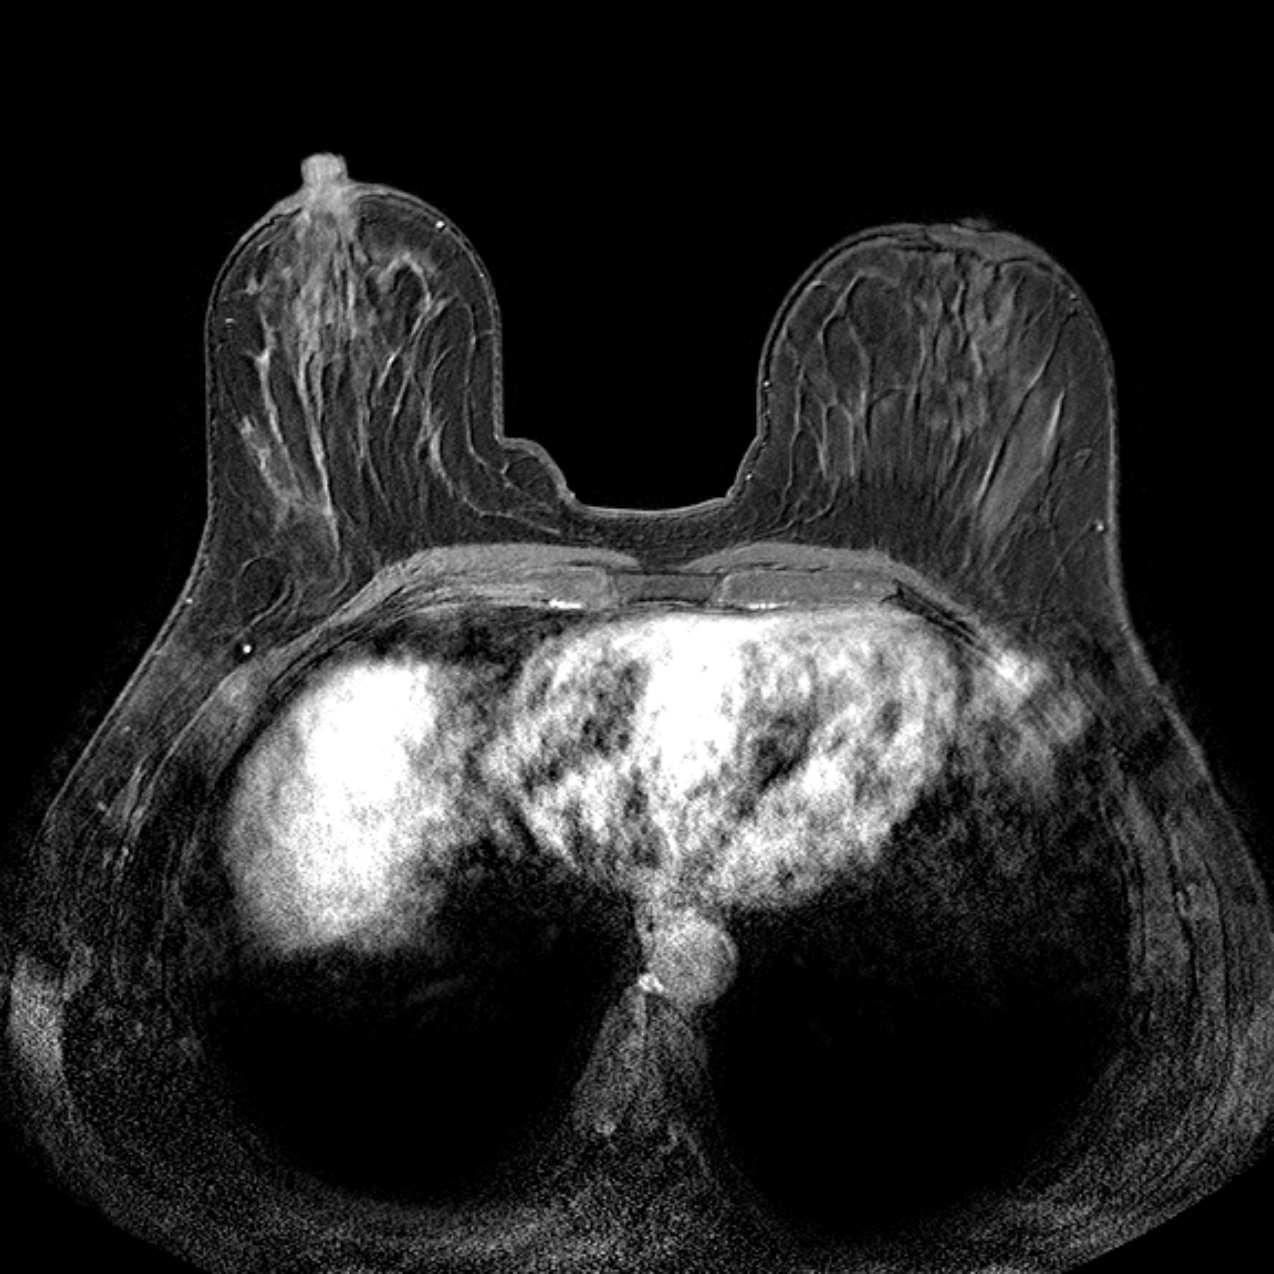

Kernspintomographie (MRT)

Wenn andere Untersuchungsmethoden keine zufriedenstellende Aussagekraft haben (etwa bei sehr „dichtem“ Drüsengewebe), kann das MRT der Brust sehr gute Dienste leisten. Das gilt sowohl in der prä-operativen Diagnostik als auch in der Nachsorge von Brustkrebs.

Bei speziellen Fragestellungen steht uns als diagnostisches Verfahren in der Radiologischen Praxis Erkelenz die Kernspintomographie der Brust zur Verfügung, für die wir auf eine langjährige Expertise zurückblicken können.